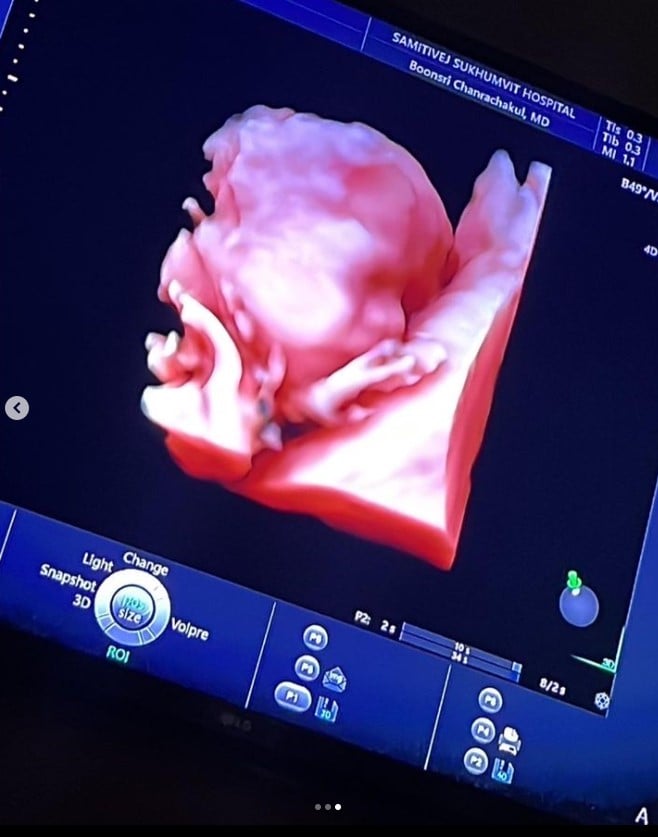

นับเป็นข่าวดีที่มาไวสุด ๆ สำหรับข่าวการตั้งครรภ์ของ จินนี่ จุฑาภัค จรรยาธนากร ลูกสาวคนโตของ ใหญ่ ฝันดี จรรยาธนากร ที่เพิ่งแต่งงานไปเมื่อช่วงเดือนมีนาคม 2566 ที่ผ่านมา งานนี้ทำใหญ่ฝันดีชื่นใจ เพราะกำลังจะมีหลานแล้ว พร้อมเผยภาพอัตราซาวด์ครั้งแรก

แต่ไฮไลท์เด็ดอยู่ที่ภาพสุดท้าย ซึ่งเป็นภาพอัตราซาวด์ท้องของจินนี่ เผยให้เห็นหลานคนแรกของใหญ่ ฝันดี จนหลายคนมาร่วมกันแสดงความยินดีกันอย่างคึกคัก อาทิ